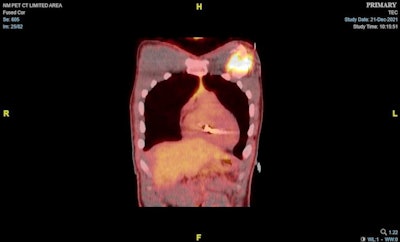

Finally, to complete the evaluation of possible cardiac sarcoidosis, a PET/CT scan was obtained, which showed no increased F-18 FDG radiotracer activity in the myocardium suggestive of the condition, the authors wrote.

"Incidentally, there was increased FDG activity posterior to the ICD along the anterior left pectoralis major muscle related to inflammation from multiple ICD shocks," they wrote.